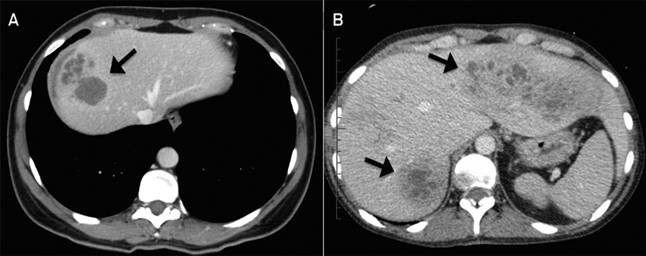

-Gan ít khi to ra ngoại trừ khi ổ tổn thương SLGL, gần bao gan ( khi đó khám sẽ xuất hiện phản ứng bao gan rất nhạy) hoặc đi kèm với một khối u gan hoặc tổ chức abces do sán (biểu hiện gan to, phì đại, có thể dưới bờ sườn bên phải 2-3cm nhưng kích thước chung không thay đổi đáng kể), khi gan to thì mềm, đôi khi sưng to lấn xuống dưới hố chậu phải (Facey và Marsden., 1960). Mức độ gan to tăng theo thời gian mắc bệnh và tiến triển của khối abces gan (Abou Basha và cs., 1989; Chen và Mott., 1990; Tchirikhtchian và cs., 1997). Một số ca gan sờ cứng, chạm ít đau, rung gan (+/-), ấn kẻ sườn không đau. Một số trường hợp có tổn thương liên quan đến phổi (như đường dò từ mặt trên và sau của gan do ổ abces lên cơ hoành rồi đến phổi phải, tạo nên một ổ dịch rất lớn chứa nhiều mật, máu và dịch tiết quánh đặc. Khi đó bệnh nhân mặc dầu điều trị xong vẫn đau cả vạt sườn bên phải;

-Triệu chứng về hô hấp: nghe phổi có thể có ran ẩm nhỏ hạt do quá trình thâm nhiễm kéo dài, thường bên (P) nhiều hơn bên (T) do sán non xâm nhập, màng phổi có thể có dịch phản ứng (Chen và Mott., 1990; Huỳnh Hồng Quang và Lê Quang Quốc Ánh, 2007), hoặc có triệu chứng thâm nhiễm dạng hội chứng Loffler như bệnh lý do giun đũa (Aliaga và cs., 1984; Huỳnh Hồng Quang., 2005; 2009)và tràn dịch màng phổi (Arias và cs., 1986; Huỳnh Hồng Quang và cs., 2006), thường gặp nhất trên hình ảnh X-quang là tràn mủ- tràn khí màng phổi (Chen và Mott., 1990), hoặc tràn dịch, tràn khí, dịch mật vào màng phổi, cơ hoành, gây khó thở hoặc tổn thương liên đới đa phủ tạng (Huỳnh Hồng Quang, Lê Quang Quốc Ánh, Bùi Quang Đi, 2006);